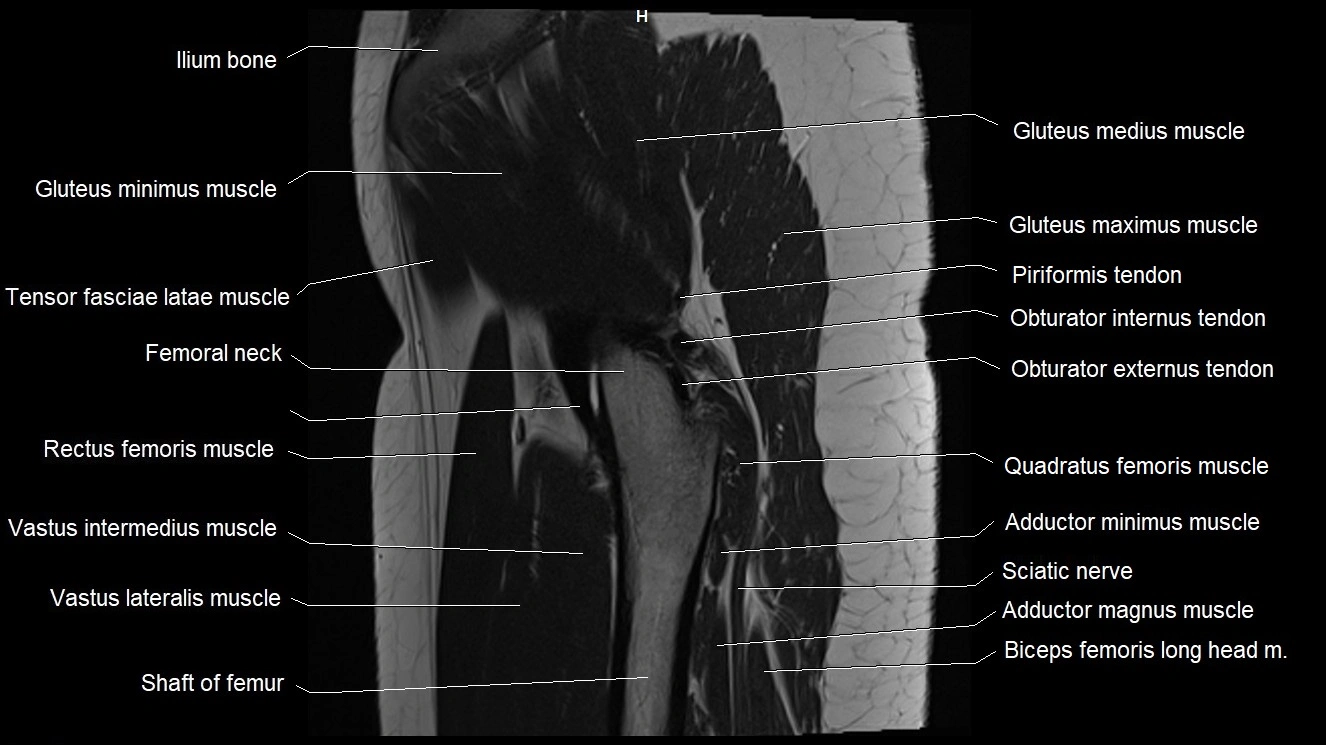

- Femoral shaft

- Femur

- Gluteus maximus muscle

- Gluteus medius muscle

- Gluteus minimus muscle

- Gluteus minimus tendon

- Iliotibial tract

- Neck of femur

- Quadratus femoris muscle

- Rectus femoris muscle

- Tensor fasciae latae muscle

- Vastus intermedius muscle

- Vastus lateralis muscle